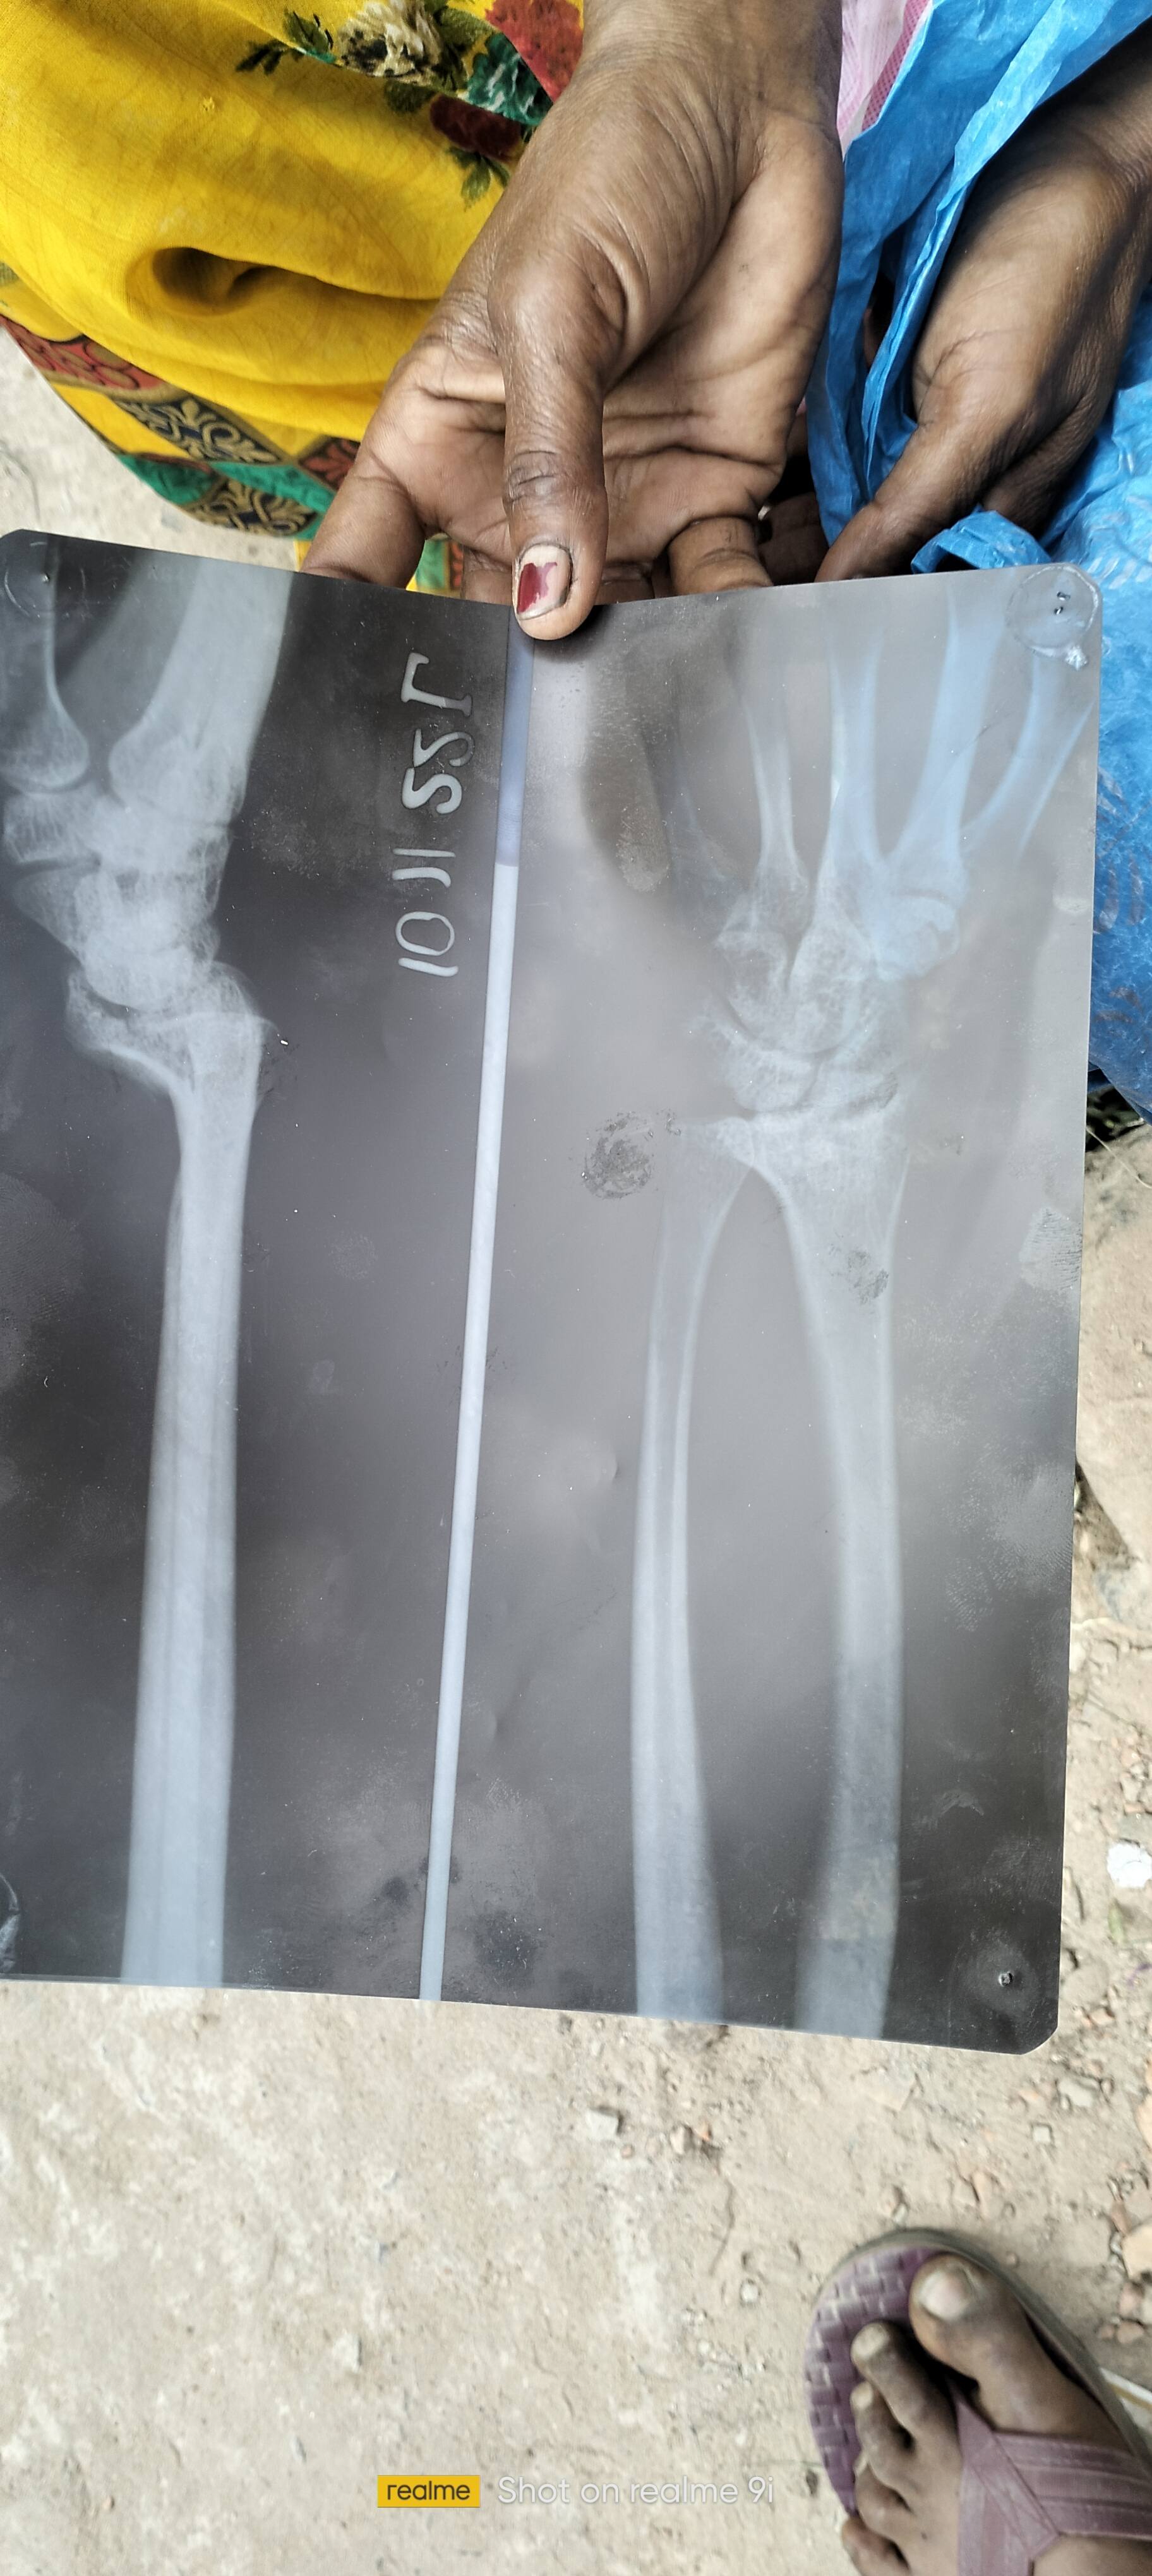

Sir hatheli m bhut drd h joint pr gir gye the kalayi me kya problem hai btaye toh sara var hatheli pr pada toh bhut drd ho rha h koi upay bataye or kya huwa h

...Read More